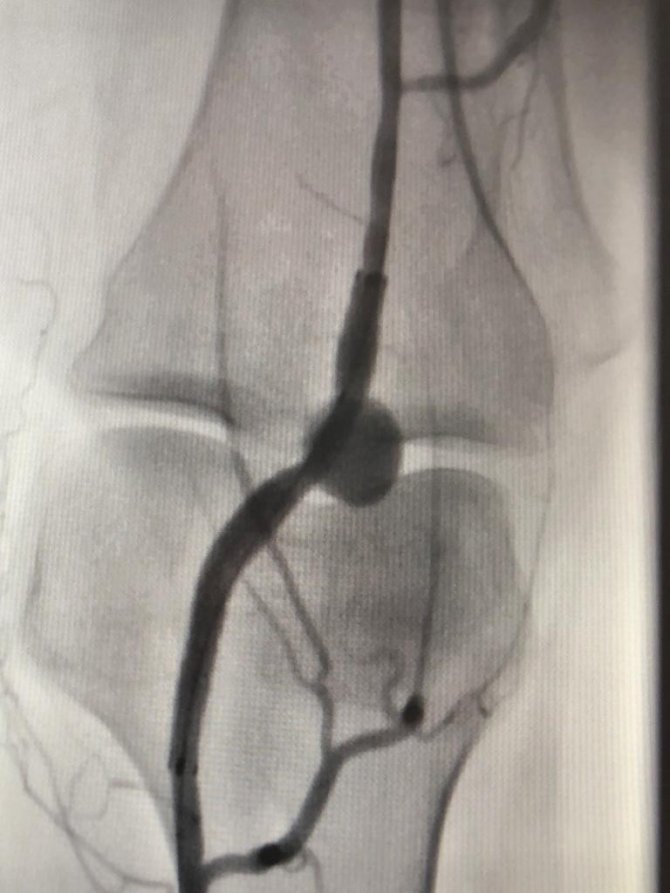

Tam donanımlı Kalp Merkezi'nde anjiyonun ardından ilk stent uygulaması da başarıyla gerçekleştirildi. 61 yaşındaki kadın hastanın bacak atardamarındaki balonlaşmaya stent-greft uygulaması yapıldı. Prof. Dr. Alptekin Yasım ve Uzman Dr. Ülker Kaya tarafından yapılan ve yaklaşık 2 saat süren operasyon ile diz bölgesindeki bacak atardamarındaki balonlaşma (anevrizma) başarı ile tedavi edildi. Genel durumu iyi olan hasta 1 gün hastanede yatırıldıktan sonra taburcu edildi.